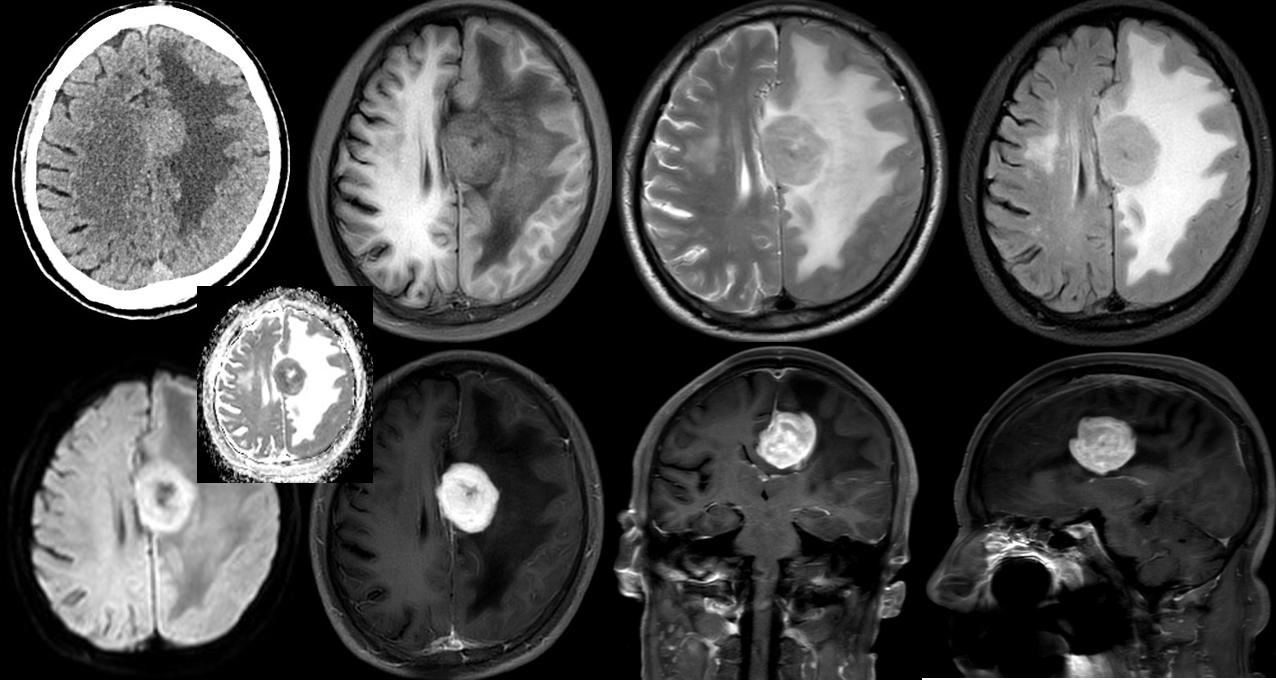

病例二

病史:男;年龄:69Y主诉:1个多月前突发右侧肢体不受控抖动,行走不稳

CT:左侧额叶大脑镰旁见一大小约2.2X28m类圆形略高密度团块,CT值43.7Hu,边界尚清,以宽基底接于大脑镰,周围额顶部脑白质内见大片低密度水肿区。双侧基底节区、放射冠区、侧脑室周围白质及皮层下区见多发斑点状、斑片状低密度灶。左侧侧脑室较对侧宽。部分脑沟、脑裂、池增宽。中线结构尚居中。

MRI:左侧颅底区可见金属伪影干扰。左侧额部大脑镰旁见一类圆形等长 T1 等长 T2异常信号T2 Flair 呈近等信号,中心见点状长T1短T2信号灶,病灶大小约3.3X3.7X3.cm,DWI(b=1000)及ADC 图示病灶轻度扩散受限,增强扫描呈明显不均匀强化,邻近部分硬脑膜可见线状强化,病灶周围脑实质见大片状长 T1 长 T2水肿信号,周围脑实质及双侧侧脑室受压变窄,左侧大脑半球脑沟裂变浅,中线结构右移。脑桥、双侧基底节区、双侧侧脑室旁白质、右侧放射冠及皮层下见多发斑点状、斑片状等长T1长T2异常信号灶,T2Flair 高信号,DMI未见明显扩散受限。右侧上颌窦粘膜增厚。

MRS示:病变区域Cho峰明显增高,NAA峰明显减低。

CT:左侧额叶占位性病变,符合脑膜瘤CT 表现,建议增强 MRI检查以除外胶质瘤;

MRI:左侧额部大脑镰旁占位性病变,符合肿瘤 MRI表现,理学检查;脑膜源性肿瘤可能性大,请结合临床。

病理:淋巴瘤。